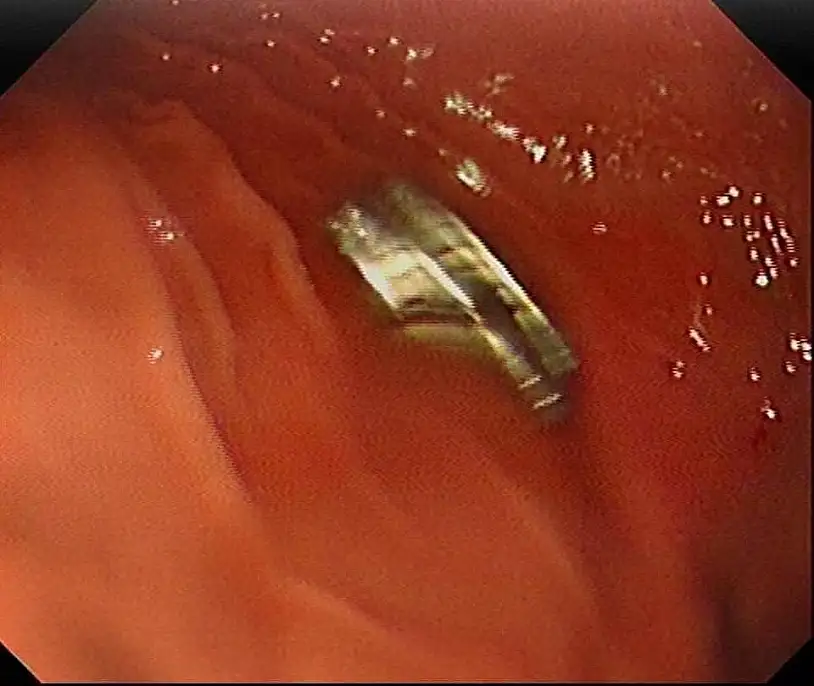

Çocuğun boğazından 19 adet mıknatıs çıkartıldı

3 yaşındaki bir çocuğun yuttuğu 19 mıknatıs, Fırat Üniversitesi Hastanesinde başarılı bir operasyon ile çıkartıldı. Edinilen bilgiye göre, Erzurum'da bir çocuk evde bulunan 19 tane mıknatısı yuttu.